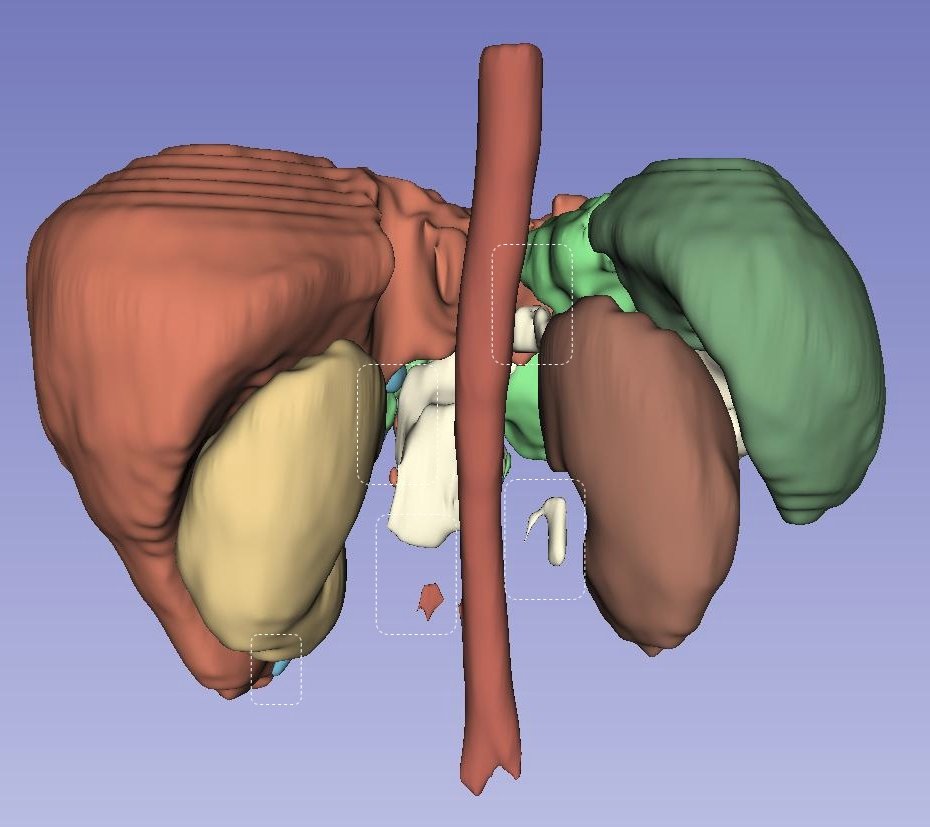

Left Atrial Dataset (LA): Figure˜5 presents a qualitative, three-dimensional visualization of various models’ performance in segmenting the Left Atrial dataset for individual patients. Each row in the figure is dedicated to the segmentation results from a single patient’s dataset, visually assessing each model’s predictive capabilities. In the case of the first patient, shown in the top row, all models except UNETR manage to generate a single entity segmentation, highlighting their ability to integrate disparate anatomical features into a unified model prediction. However, a common challenge across all models is the accurate segmentation of the right corner of the atrium, suggesting a shared area of potential improvement. For the second patient, delineated in the second row, it is discernible that competing models struggle to accurately segment the entirety of the ground truth, resulting in multiple segmented instances rather than a single cohesive structure. Contrarily, LHU-Net succeeds in rendering a single, contiguous segmentation that closely resembles the ground truth, demonstrating its ability to produce smoother and more coherent segmentations. The last patient, as illustrated in the bottom row, presents a challenging case where all models exhibit a tendency for over-segmentation at the base of the atrium. This is indicative of the intrinsic complexity of accurately delineating this anatomical region. Nevertheless, it is worth noting that certain models, specifically UNETR and SwinUNETR-V2, additionally exhibit under-segmentation in other areas, further complicating the segmentation task. In summation, the visualizations in Figure˜5 suggest that LHU-Net consistently generates more robust and smoother segmentations, avoiding the creation of extraneous entities.

NIH pancreas dataset (CT-82): Figure˜6 provides a three-dimensional visualization for the qualitative analysis of pancreatic segmentation across several state-of-the-art models. Each row visually represents the segmentation results from an individual patient’s dataset, offering insight into the predictive precision of each model. For the first patient, illustrated in the first row, it is observable that all models, except for LHU-Net, UNETR++, and SwinUNETR-v2, could not produce a singular, cohesive entity representing the organ. UNETR++ generates a single entity; however, it significantly under-segments the pancreas, failing to capture the complete anatomical structure. In stark contrast, LHU-Net achieves a segmentation that closely approximates the ground truth, underscoring its capability to preserve the organ’s integrity in the segmentation process. The second patient’s data, depicted in the second row, further accentuates the proficiency of LHU-Net in producing a smooth and robust segmentation, particularly when compared to its counterparts. Notably, UNETR++ exhibits a fragmentation in the segmentation, resulting in multiple entities and suggesting a lack of robustness within this dataset. The visualization of the third patient, in the third row, reveals the intrinsic challenges posed by this dataset, as all models predict multiple entities. Nonetheless, LHU-Net distinguishes itself by accurately segmenting the predominant portion that aligns with the ground truth and generating only a minor secondary entity. This contrasts with the other models, which produce multiple, larger erroneous segments, thus compromising the segmentation’s fidelity. Overall, LHU-Net demonstrates superior robustness and smoothness in its segmentation outputs, consistently predicting the pancreas with a higher degree of anatomical accuracy.